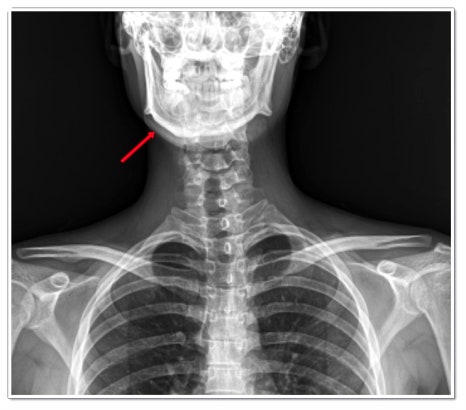

예를 들어, 거북목 자세처럼 고개가 앞으로 빠져 있으면 머리의 무게 중심이 턱관절 쪽으로 쏠리게 됩니다.

이때 관절 안의 원판이 밀려나며 ‘딱’ 소리가 나거나 턱이 한쪽으로 당겨져 불편함이 생기죠.

이렇게 골반이 비틀리면 머리의 중심선이 기울고, 결국 턱관절의 위치도 틀어지게 됩니다.